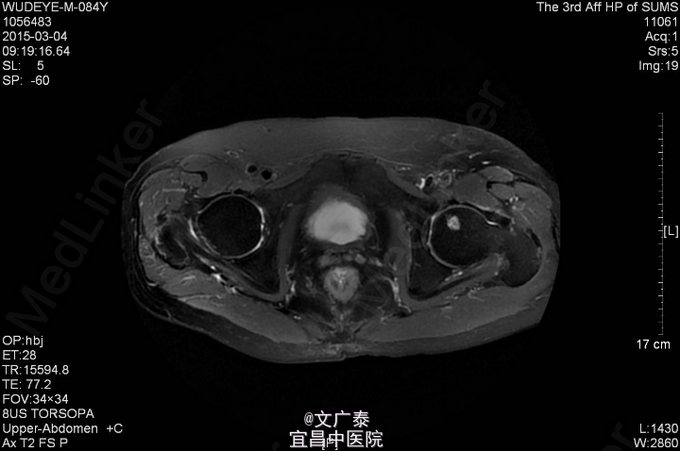

1、TURP加双侧睾丸切除术后11年 2、患者于11年前在本院行前列腺电切术加双侧睾丸切除术后,术后病理回报:前列腺腺癌,(Gleason评分:4+5=9分)。术后予以康士得(50mg qd )内分泌治疗2年后改用福至尔(250mg tid)治疗至今。复查tPSA: 2011.02 tPSA:1.00 ng/L,2012.02 tPSA:0.804 ng/L,2013.02 tPSA:1.23 ng/L,2014.11 tPSA:2.57 ng/L。

3、直肠指检:肛门括约肌正常,前列腺不大,无触痛,表面光滑,质韧,边缘清楚,中央沟存在,未触及明显结节,指套未见染血。余无异常 4、盆腔MR:前列腺癌术后。核素PET/CT全身:1.前列腺癌术后,局部软组织灶,未见明显异常代谢,考虑疤痕形成可能性大;